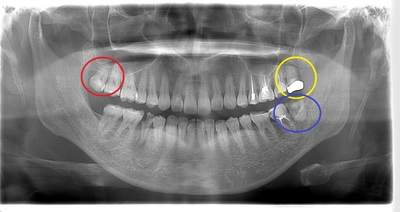

左下の歯茎が腫れている親知らずの症例

- 抜歯前写真(レントゲン、CT等)

左下の親知らず周囲歯肉が腫れていました。

また、手前の歯との間で虫歯もできていました。

3分割して抜歯しました。

| 年齢 | 20代・女性 |

|---|---|

| 主訴 | 左下の歯茎が腫れている |

| 適応するプラン | スタンダード親知らず抜歯プラン |

| 親知らずの生え方 | 歯茎から少し頭が出ている |

| 抜歯時間 | 15分 |

| 費用 | 約7,000円 |

| 抜歯内容 | 下顎の親知らずの抜歯希望の患者様です。 智歯周囲炎となっており、初診時では麻酔が効きづらい旨をお話しし、初診時は抗生物質をお出ししました。1週間後、ある程度歯肉の炎症がとれたことを確認して抜歯を行いました。 麻酔を行い、遠心(親知らずの奥側)歯肉と、手前の歯の頬側の歯肉を切開しました。 歯茎を開いて、手前の歯と引っかかっている部分をカットしました。 その後、骨からでている歯冠部(頭の部分)をカットしました。 その後へーベルで歯根(骨に埋まっている部分)を脱臼し、抜歯を終えました。 切開した歯茎を3針縫って、治療終了となりました。 歯茎を切ったため、3日ほど腫れぼったい感じがあったようですが、痛みはほとんどなく、治癒に向かいました。 |